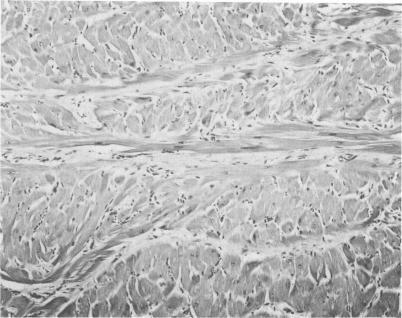

Gross anatomic features and the pattern and extent of cardiac muscle cell disorganization were studied in the hearts of 51 with spontaneously occurring hypertrophic cardiomyopathy. Each cat had a hypertrophied, but nondilated, left ventricle. Ventricular septal disorganization was extensive, involving 5% or more of the relevant areas of the tissue section, in 14 (27%) of the 51 cats. Marked septal disorganization occurred only in those cats with asymmetric septal hypertrophy (ventricular septal to left ventricular free wall thickness ratio of greater than or equal to 1.1) Disorganization of cardiac muscle cells was uncommon and less extensive in the left ventricular free wall of the cats with hypertrophic cardiomyopathy. Disorganization involved the free wall of only 7 cats, each with asymmetric septal hypertrophy, and occupied greater than 5% of the free wall tissue sections in just 3. Hence, about one fourth of this population of cats had hypertrophic cardiomyopathy resembling the human form of this disease, with asymmetric left ventricular hypertrophy and marked disorganization of cardiac muscle cells in the ventricular septum. The majority of cats (about 75%), however, demonstrated a form of hypertrophic cardiomyopathy characterized by symmetric ventricular hypertrophy and normal arrangement of cardiac muscle cells.

对51只患有自发性肥厚型心肌病的猫的心脏进行了大体解剖特征以及心肌细胞紊乱的模式和范围的研究。每只猫都有一个肥厚但未扩张的左心室。在51只猫中的14只(27%),室间隔紊乱广泛,累及组织切片相关区域的5%或更多。明显的间隔紊乱仅发生在那些伴有不对称间隔肥厚(室间隔与左心室游离壁厚度比大于或等于1.1)的猫中。在肥厚型心肌病的猫的左心室游离壁中,心肌细胞紊乱不常见且范围较小。紊乱仅累及7只猫的游离壁,每只猫都有不对称间隔肥厚,且仅在3只猫中占据游离壁组织切片的5%以上。因此,这群猫中约四分之一患有类似于人类这种疾病形式的肥厚型心肌病,表现为不对称左心室肥厚和室间隔心肌细胞明显紊乱。然而,大多数猫(约75%)表现出一种以对称性心室肥厚和心肌细胞正常排列为特征的肥厚型心肌病形式。